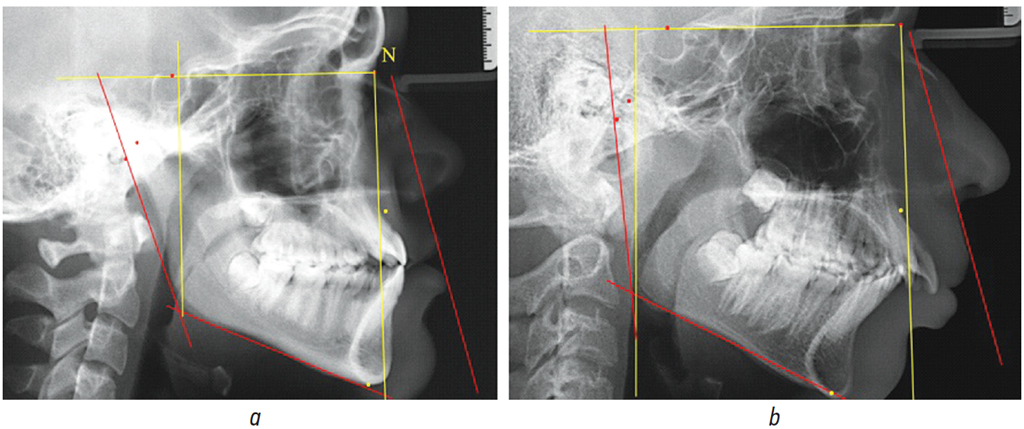

Рис. 1. Расположение ориентировочных точек (а) и диагностических линий (b) для исследования составных частей нижнечелюстного угла при нейтральном типе роста

Fig. 1. Reference points (а) and diagnostic lines (b) for assessing mandibular angle components in neutral growth

В данной группе среднее значение нижнечелюстного угла составило 120,81° ± 1,46°. При этом, угол отклонения ветви от гониональной вертикали (угол Go’-Go-Co) составил 7,46° ± 0,93°.

Вторая составляющая нижнечелюстного угла, а именно угол Go’-Go-Me, составила 113,41° ± 1,43°. При анализе углов тела нижней челюсти с альвеолярной ее частью было отмечено, что угол Go’-Go-В составлял 95,22° ± 2,14°, а величина угла тела нижней челюсти В-Go-Me — 18,13° ± 1,93° (рис. 1).

В исследуемой группе угол, образованный назальной вертикалью лица и окклюзионной плоскостью, составлял 81,85° ± 2,09°, с мандибулярной плоскостью — 66,65° ± 1,43°, а с линией В-Go — 84,78° ± 2,14°.